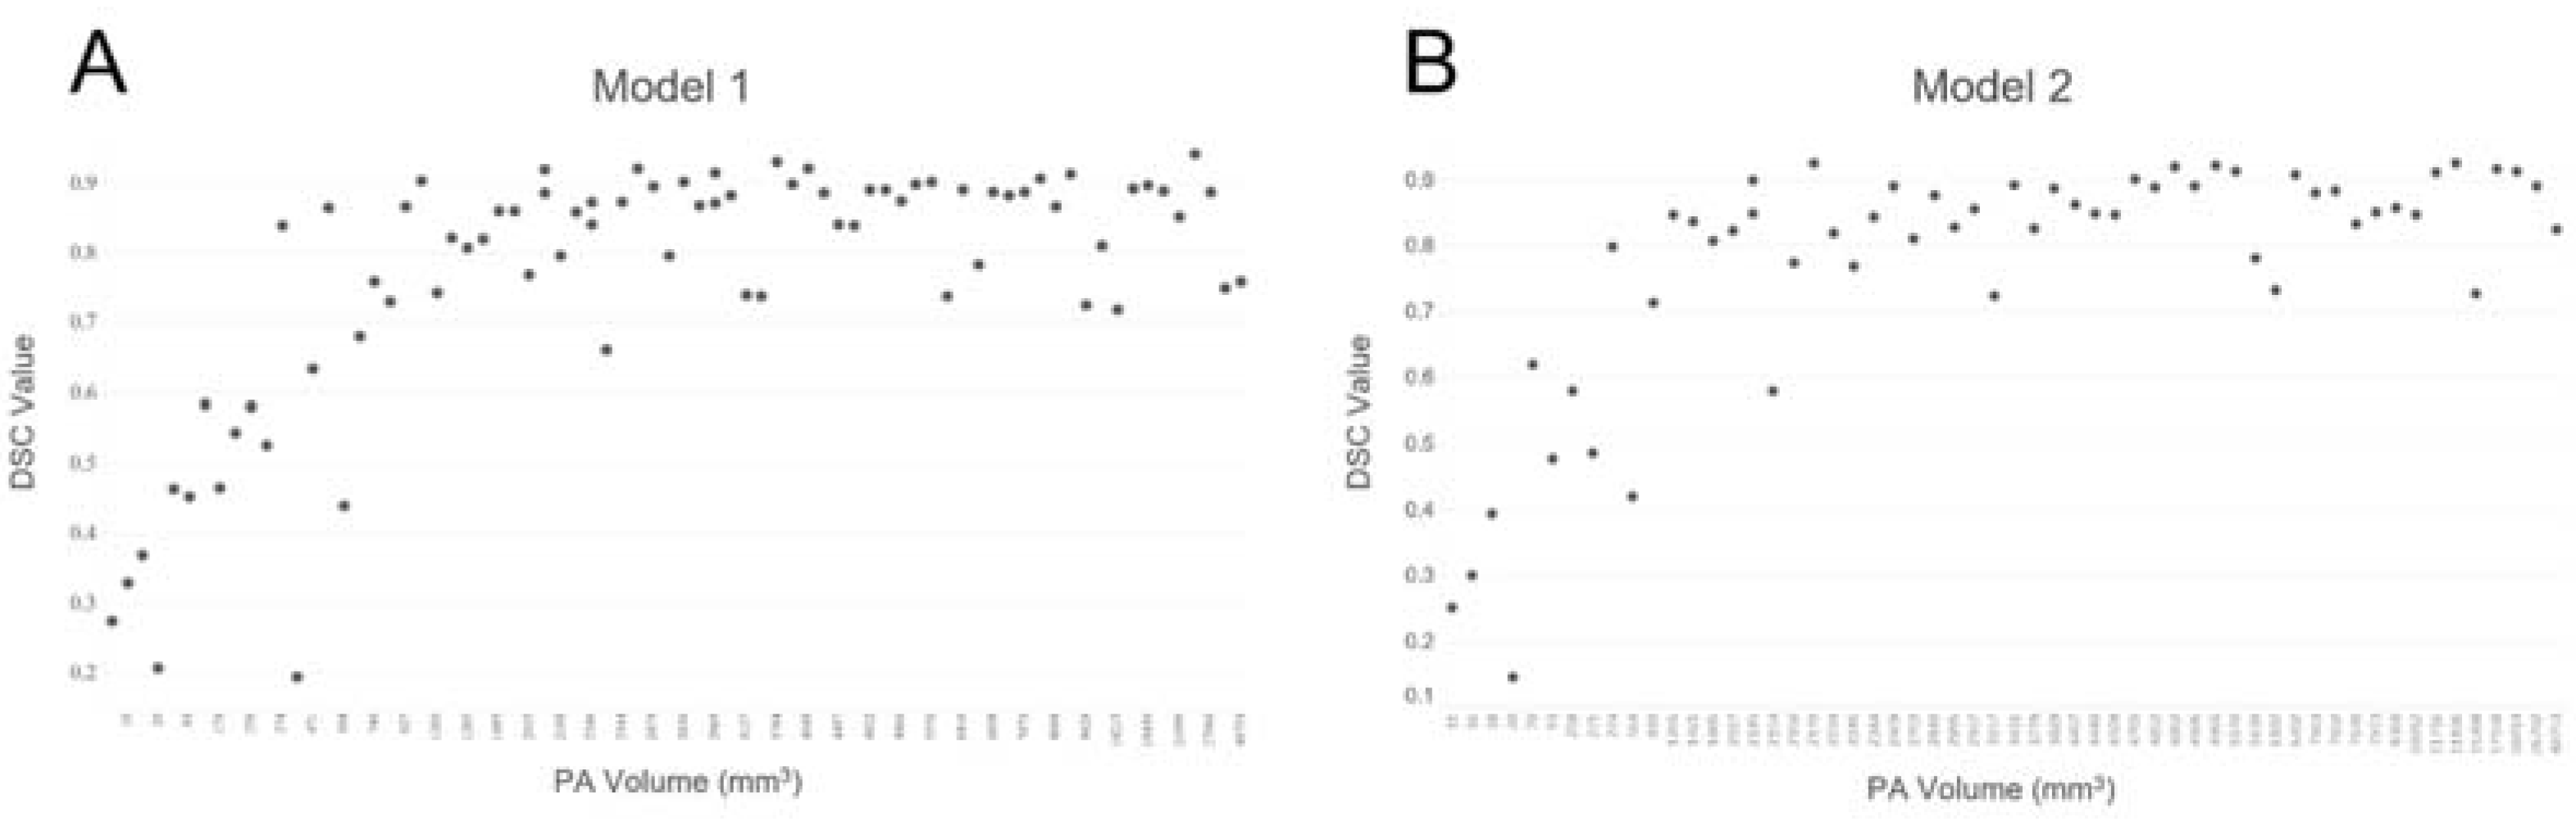

3.6. The Relationship between DSC Values and PA Volumes

3.4. Model Performance in the Testing Dataset

3.5. Performance Comparison between the Two Models